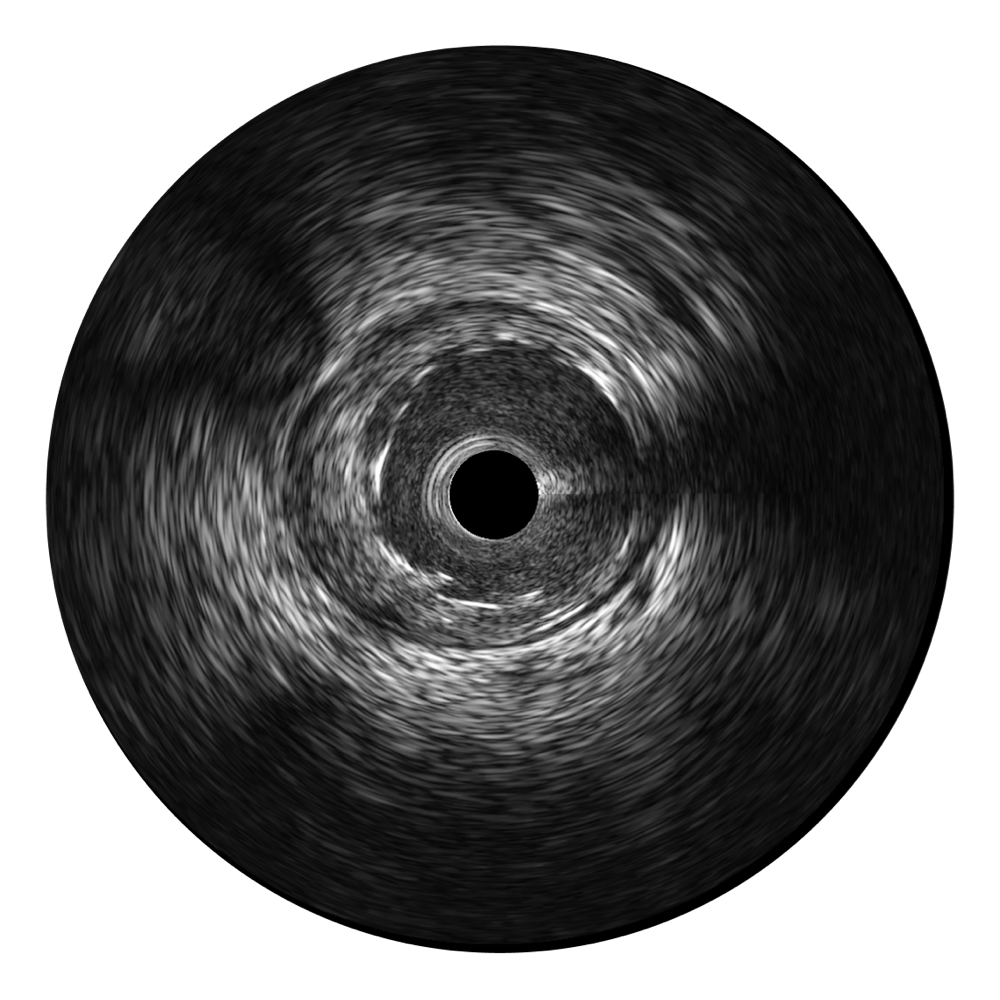

对比传统IVUS导管成像,竞技宝(JJB)官方网站宽频IVUS图像的近场支架梁显影更细腻,远场中膜外血管仍清晰可辨,兼顾远中近,兼顾分辨力与穿透深度